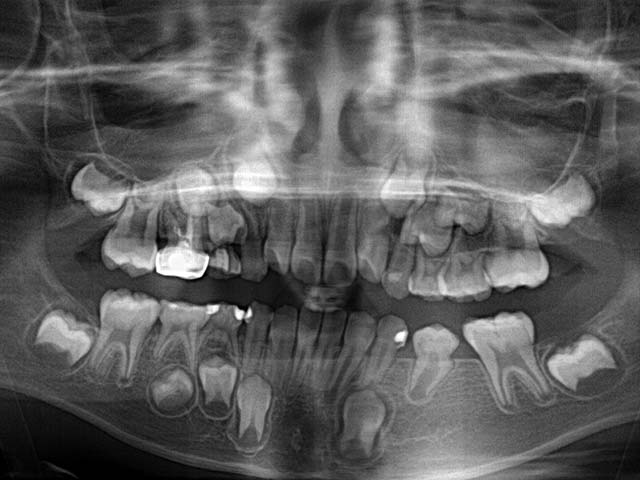

以下可以看到混合齒列期乳牙與恆牙在口內的對應位置

正常混合齒列